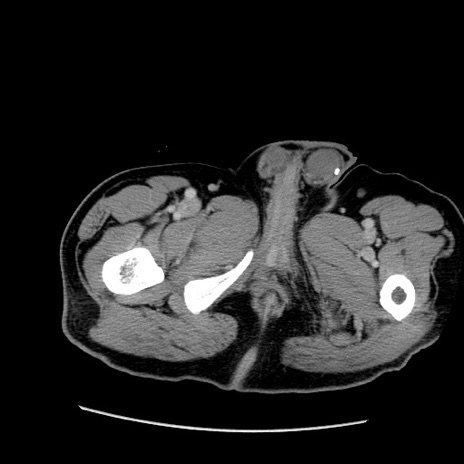

冠状断像

【症例】50歳代男性

【主訴】腹痛

【現病歴】AVMからの被殻出血のため回復期リハ病棟入院中。 本日午後3時頃急に下腹部痛が出現した。

【既往歴】AVM、被殻出血、虫垂炎、高血圧

【身体所見】意識晴明、左半身不全麻痺、会話の理解は良好、36.5°C、腹部:膨隆、全体に板状硬、下腹部正中に圧痛点あり、反跳痛-、筋性防御不明、右下腹部にope scar

【データ】WBC 9400、CRP 0.06